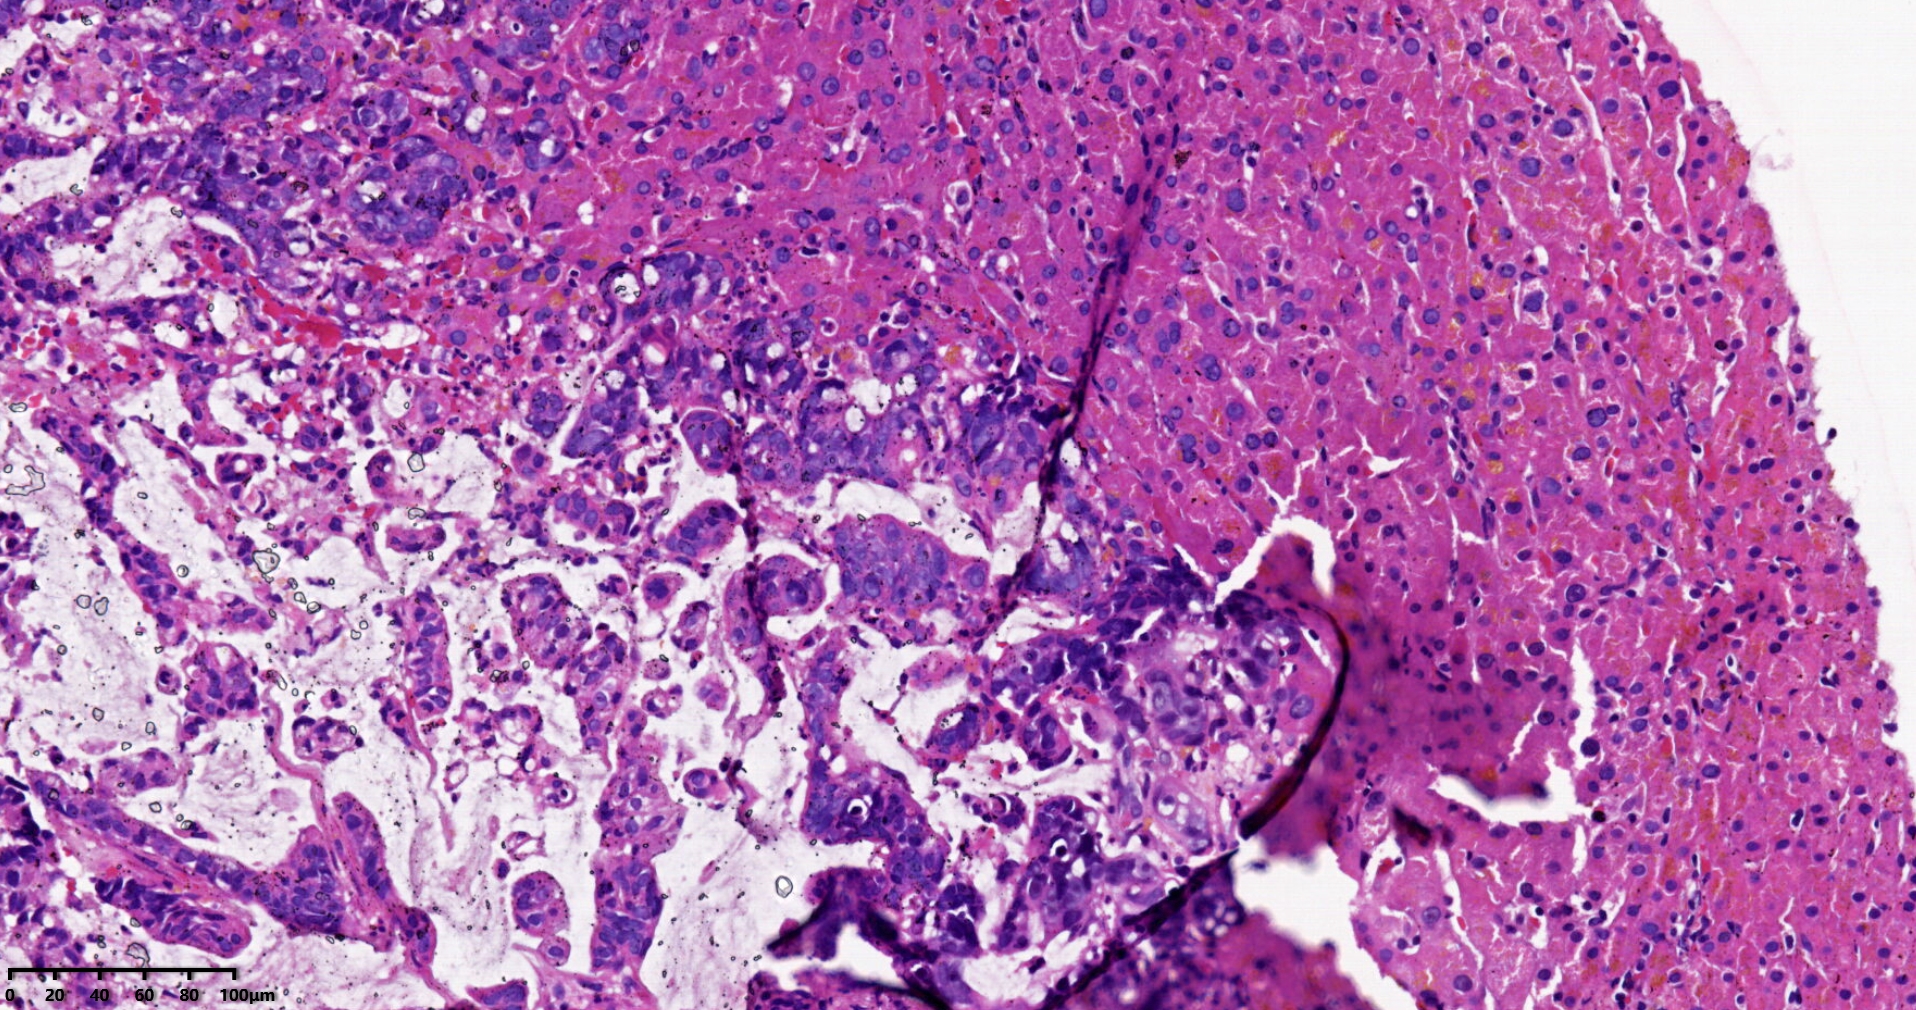

考虑符合:肝内胆管癌

• rys114:  老师,免疫组化ck7-,ck20+,支持诊断吗?

• whyang315:  当然!

问一问临床其他部位有没有肿瘤病史。

考虑转移性黏液腺癌,消化道来源可能,建议做免疫组化,排除胆管源性。